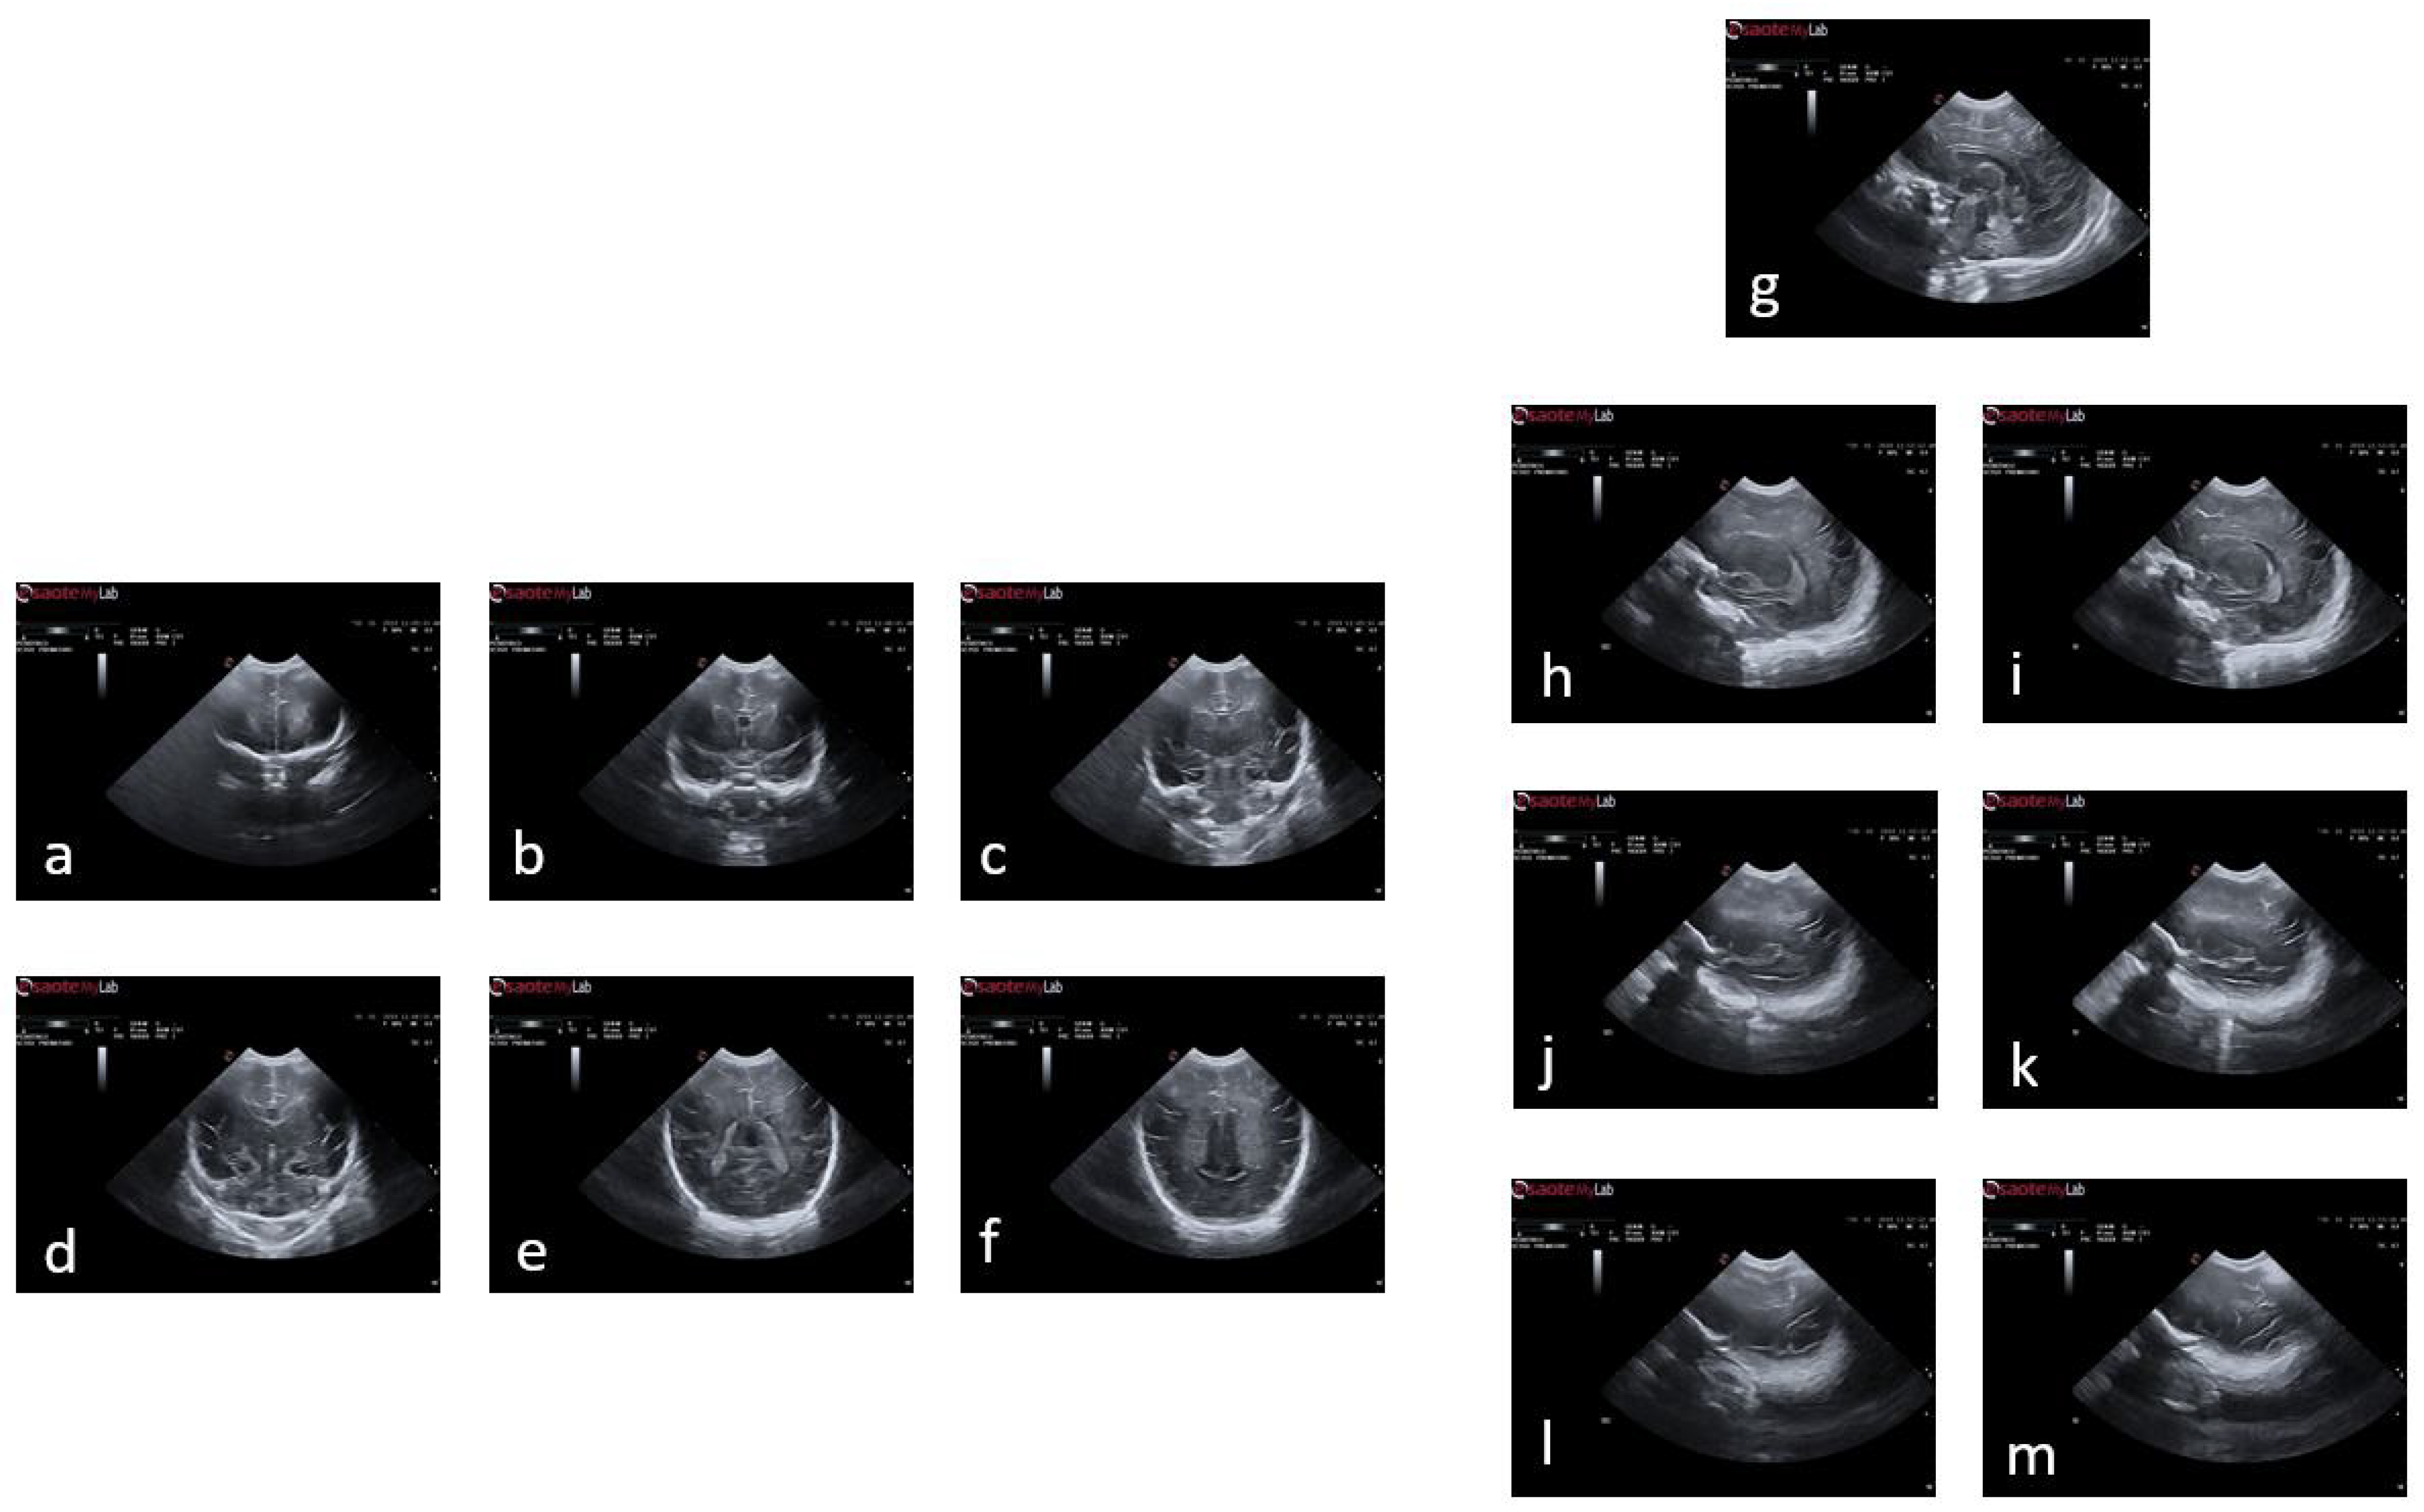

Figure 2 illustrates an example of a premature baby acquisition for both the coronal and sagittal planes. The images of each infant were acquired over several weeks, ranging from 24 to 30 weeks. The images were obtained following anatomical references for different planes:

• Coronal plane: orbital border ( c 1 ), sphenoidal ridge ( c 2 ), foramina of Monro and third ventricle ( c 3 ), fourth ventricle ( c 4 ), choroid plexus ( c 5 ), and visibility of the parietooccipital sulcus in the inferior tier of the image ( c 6 ).

• Sagittal plane: midsagittal ( s 1 ), lateral ventricles ( s 2 l , s 2 r ), lateral fissure ( s 3 r ), and lateral fissure at the bottom of the image ( s 4 l , s 4 r ).

Figure 2. Plans used in the study of a premature baby. For the coronal plane and following the alphabetical order from (a) to (f), we have the planes of c 1 , c 2 , c 3 , c 4 , c 5 , and c 6 ; and following the same order but starting with (g) and ending with (m), the sagittal planes s 1 , s 2 l , s 2 r , s 3 l , s 3 r , s 4 l , and s 4 r .